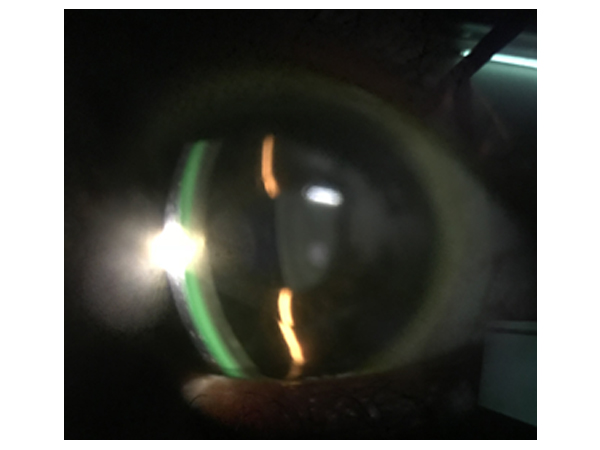

SL Photography

This involves Photographic record keeping of eye lesions with the help of slit lamp and camera